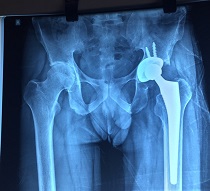

Bilateral Thr

Bilateral Thr Male

Preop AP View

Thr 25 Yea Male

Thr 25 Yea Male 4

Joint Replacement Surgery